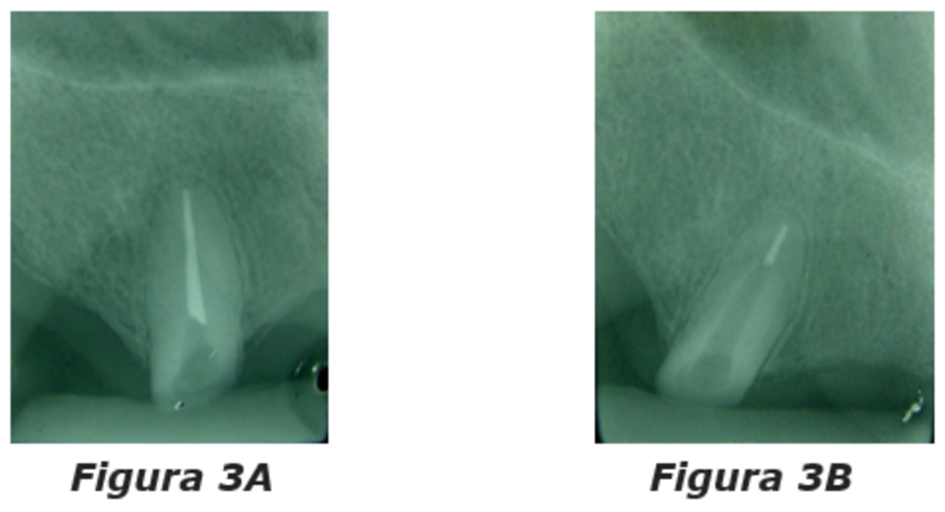

Importante ressaltar que os dentes pilares que farão o suporte da overdenture parcial removível dentorretida precisam apresentar ótimo estado periodontal e endodôntico – ou seja, tratados endodonticamente e sem lesões e com periodonto de suporte e sustentação sem bolsas ou sinais de inflamação, como ilustrado nas figuras 3A e 3B, e tudo isso atestado clínica e radiograficamente.

Figuras 3A e 3B: em 3A pode ser observado o estado adequado do tratamento endodôntico realizado, assim como a ausência de espessamento do ligamento periodontal. Em 3B notamos o conduto já desobturado como mandam as regras para a instalação dos retentores radiculares, ou seja, 2/3 de desobturação do conduto radicular.